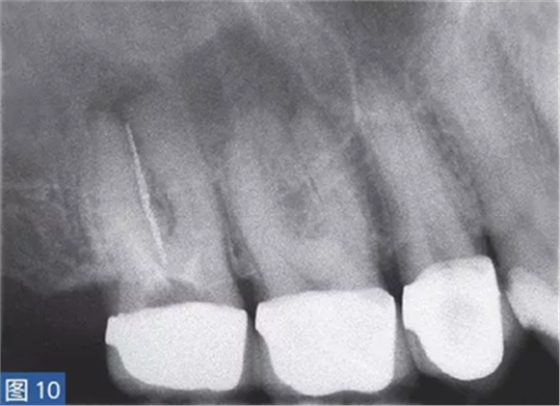

慢性根尖周膿腫(圖10 和11)是由長(zhǎng)期持續(xù)的炎癥引起的。膿液穿通骨和口腔黏膜,并通過(guò)口腔黏膜或上皮的瘺管流出。這些通到表皮的瘺管通常可能作為皮膚損傷而被錯(cuò)誤處置。此外,瘺管也可能存在于牙周并通過(guò)齦溝引流。瘺管可以部分或完全地被上皮所包繞,這些上皮又被炎性結(jié)締組織包圍。

臨床診斷顯示牙髓電活力測(cè)試結(jié)果為陰性。除非瘺管閉合,否則叩診和觸診通常都不會(huì)引起疼痛。放射學(xué)檢查,根尖周組織表現(xiàn)從無(wú)變化到發(fā)生明顯變化。

圖10:17 牙齒CAA。術(shù)前放射學(xué)檢查,利用牙膠尖顯示瘺管?;颊咭?7 牙齒局部瘺管而前來(lái)就診,訴無(wú)特殊臨床癥狀。

圖11: 17 牙齒CAA。根管治療12 個(gè)月后。